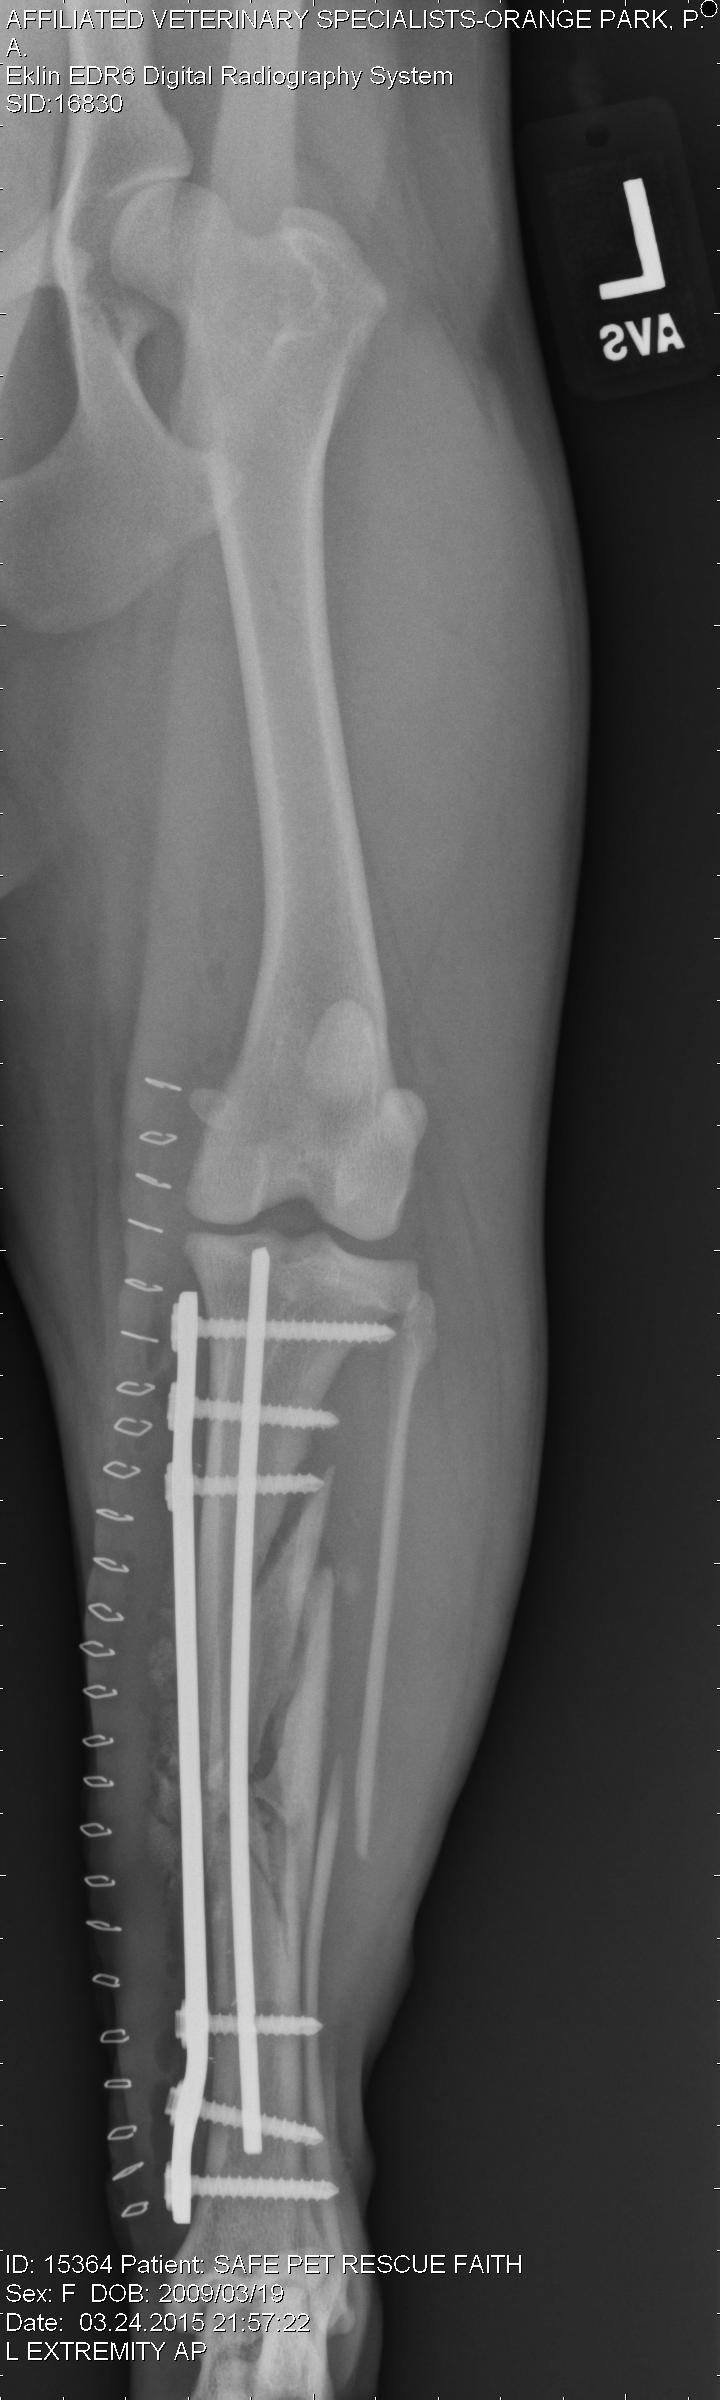

An experienced veterinarian will be able to quickly diagnose this condition, based on signalment (breed), clinical signs, and physical examination. Radiographs (X-rays) generally leave little doubt, as there are “tell-tale” signs seen on x-rays. Blood work will also be performed to assess values such as red blood cell concentration, electrolyte abnormalities, lactate, etc all factors that will be used to guide initial stabilization and treatment prior to surgery. Once diagnosed, surgery is required. If surgery is not feasible (patient is not able to be stabilized, owner unable to move forward with surgery, etc), humane euthanasia will be likely recommended.

This is a right lateral abdominal x-ray. Note the large, dilated stomach and evidence of the duodenum (intestine) just above the stomach and below the spinal column.